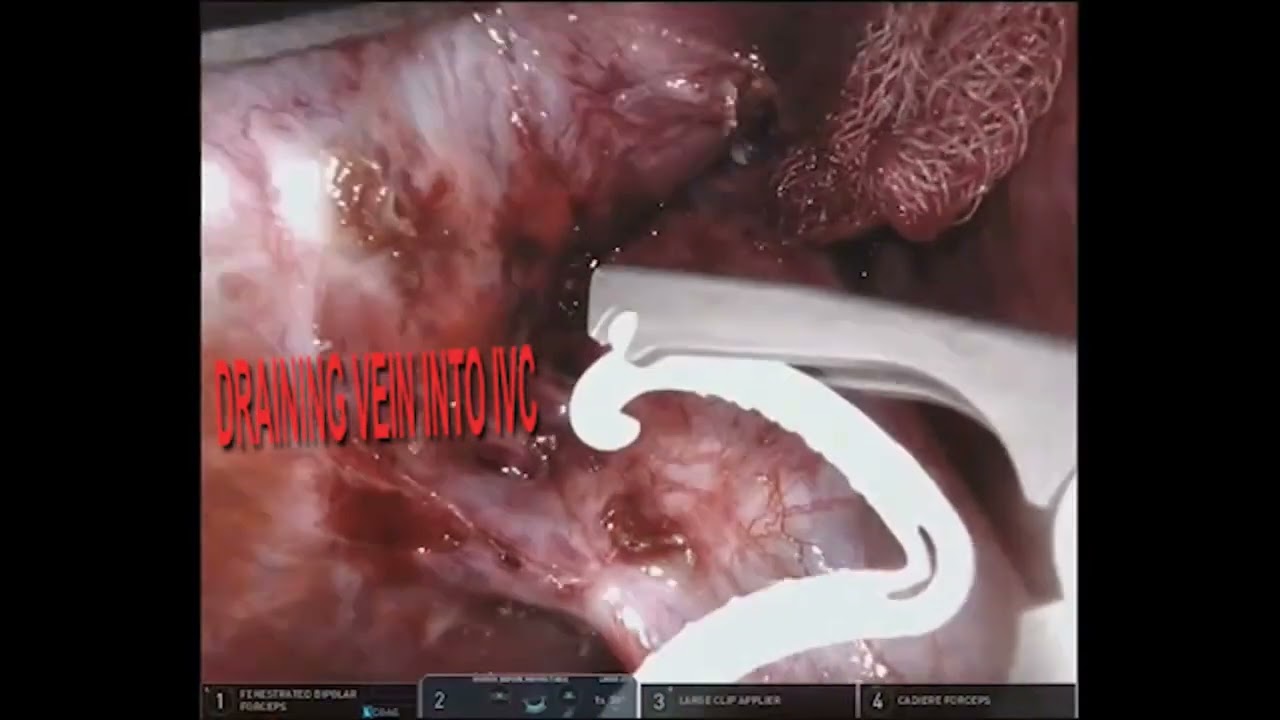

Jaipur Saturday Session 7 IVC Thrombus

Jaipur Saturday Session 5 Hepato-Pancreato-Billiary Surgery

#360 Robotic Assisted Right Adrenalectomy with IVC thrombectomy Dr. Deepak Kaddu

# 209 Robotic pancreatic tail resection Kimura procedure- Dr. George van der Schelling